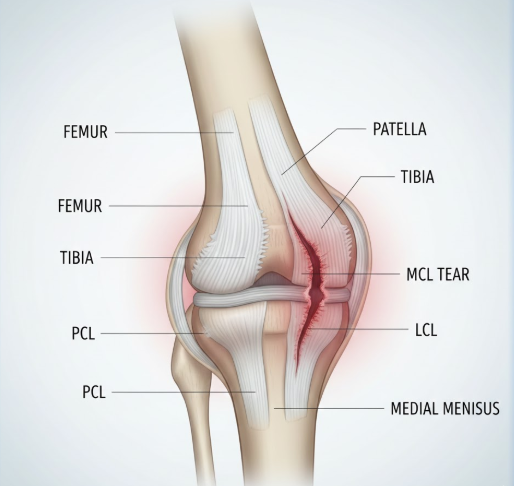

2) 무릎 안쪽 통증의 원인

- 내측 측부인대 손상

- 무릎 안쪽 통증의 대표적 원인

- 무릎이 바깥쪽으로 꺾이는 외력을 받을 때 안쪽 인대가 늘어나거나 찢어짐

- 걸을 때 안쪽에 찌르는 듯한 통증 발생

- 무릎이 불안정하게 느껴짐

- 반월상연골 파열

- 무릎 안쪽과 바깥쪽 모두에서 발생 가능, 내측이 더 흔함

- 무릎을 비트는 동작에서 연골 찢어짐

- '뚝' 하는 소리와 함께 통증 발생

- 무릎이 잘 펴지지 않는 증상 나타남